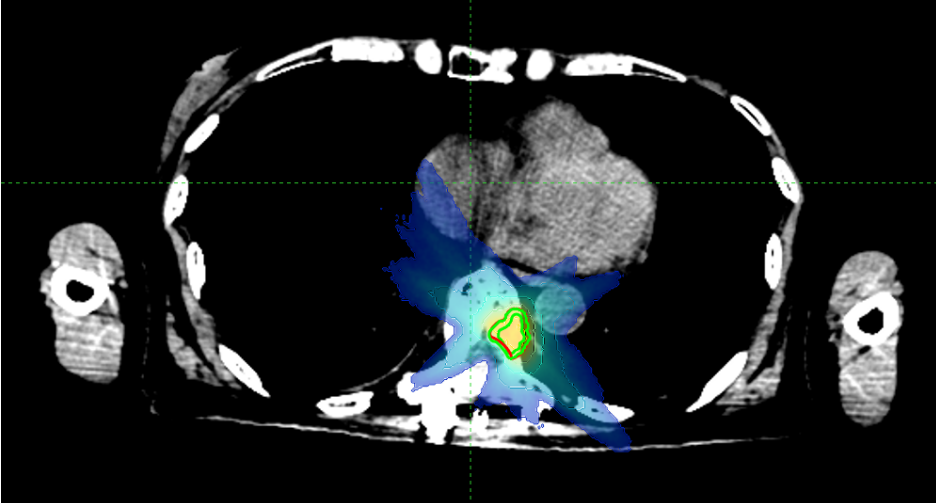

据罗女士的主管医师周霞副主任医师介绍,因T9病灶靠近脊髓附近,如果常规放疗,很可能会造成脊髓不可逆的损伤。于是慕名来到我院,胸部放疗科周霞副主任医师为她量身制定了放疗计划,近期开始进行射波刀放射治疗。

周霞介绍,脊柱骨转移瘤是射波刀的拿手好戏。脊髓往往对近在咫尺的脊柱骨转移瘤避无可避,而精准的照射在给它温柔的保护之余,高剂量射线痛击骨内病灶,可以达到缓解疼痛、控制肿瘤的目的。